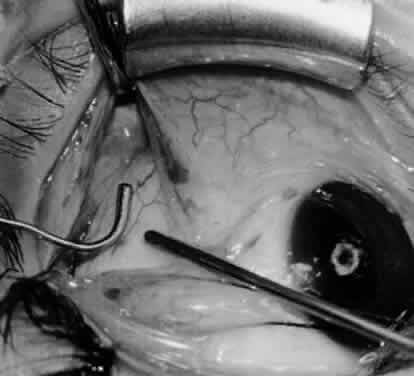

Fig. 7. A Westcott scissor is used gently to open a space beneath the elevated inferior oblique muscle and allow placement of a Green muscle hook.

Fig. 8. The Green muscle hook is placed beneath the belly of the inferior oblique muscle, and the eye is retracted nasally.